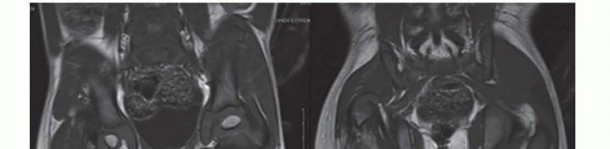

in the proximal femur, and the CFD is classified as type 1b. The arthrogram is also useful to differentiate between Paley types 2a and 2b. Both 2a and 2b might have a femoral head present; the difference is whether the femoral head is fused to the acetabulum or not. If dye can be injected into a joint space, the hip can usually be classified as type 2a. In some cases of type 2a, the dye can be seen to outline a cleft through the femoral neck. Illustration 8 for Treatment for Congenital Femoral Deficiency: What You Need to Know Illustration 9 for Treatment for Congenital Femoral Deficiency: What You Need to Know FIG 4 • MRIs of Paley type 2 CFD. The femoral head is clearly seen (A), and in a separate cut, one sees the proximal femur in a different plane (B). *

Other imaging studies that are useful include magnetic resonance imaging (MRI) and arthrography of the hips. All Paley types 1b and 2 should have an MRI after age 18 months to confirm whether there is a cartilaginous connection between the femoral head and shaft (

FIG 4 *).